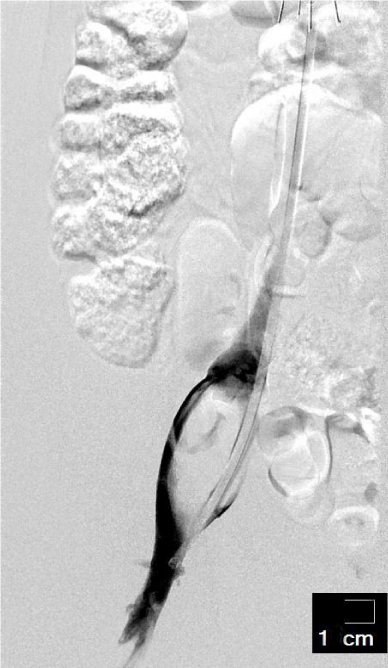

The patient was admitted in interventional ward when her symptoms had no change after one week’s medication therapy. Though there were no abnormalities in her blood coagulation tests, she was given an inferior vena cava filter, and also a catheter was inserted inside the lesion. Several attempts at retrieving thrombi were made when the lesion was detected under DSA (Figure 1), but nothing was able to be dislodged. After her interventional procedure, Urokinase 0.3 million units Q12 was given through pedal vein, and Nadroparin 3800 unites was given subdermal. Another set of CBC and coagulation test were ordered 36 hours later; both came back normal. Her physical exams were roughly the same compared to admission.

Figure 2: DSA showed a bulging lesion within the iliac vein.